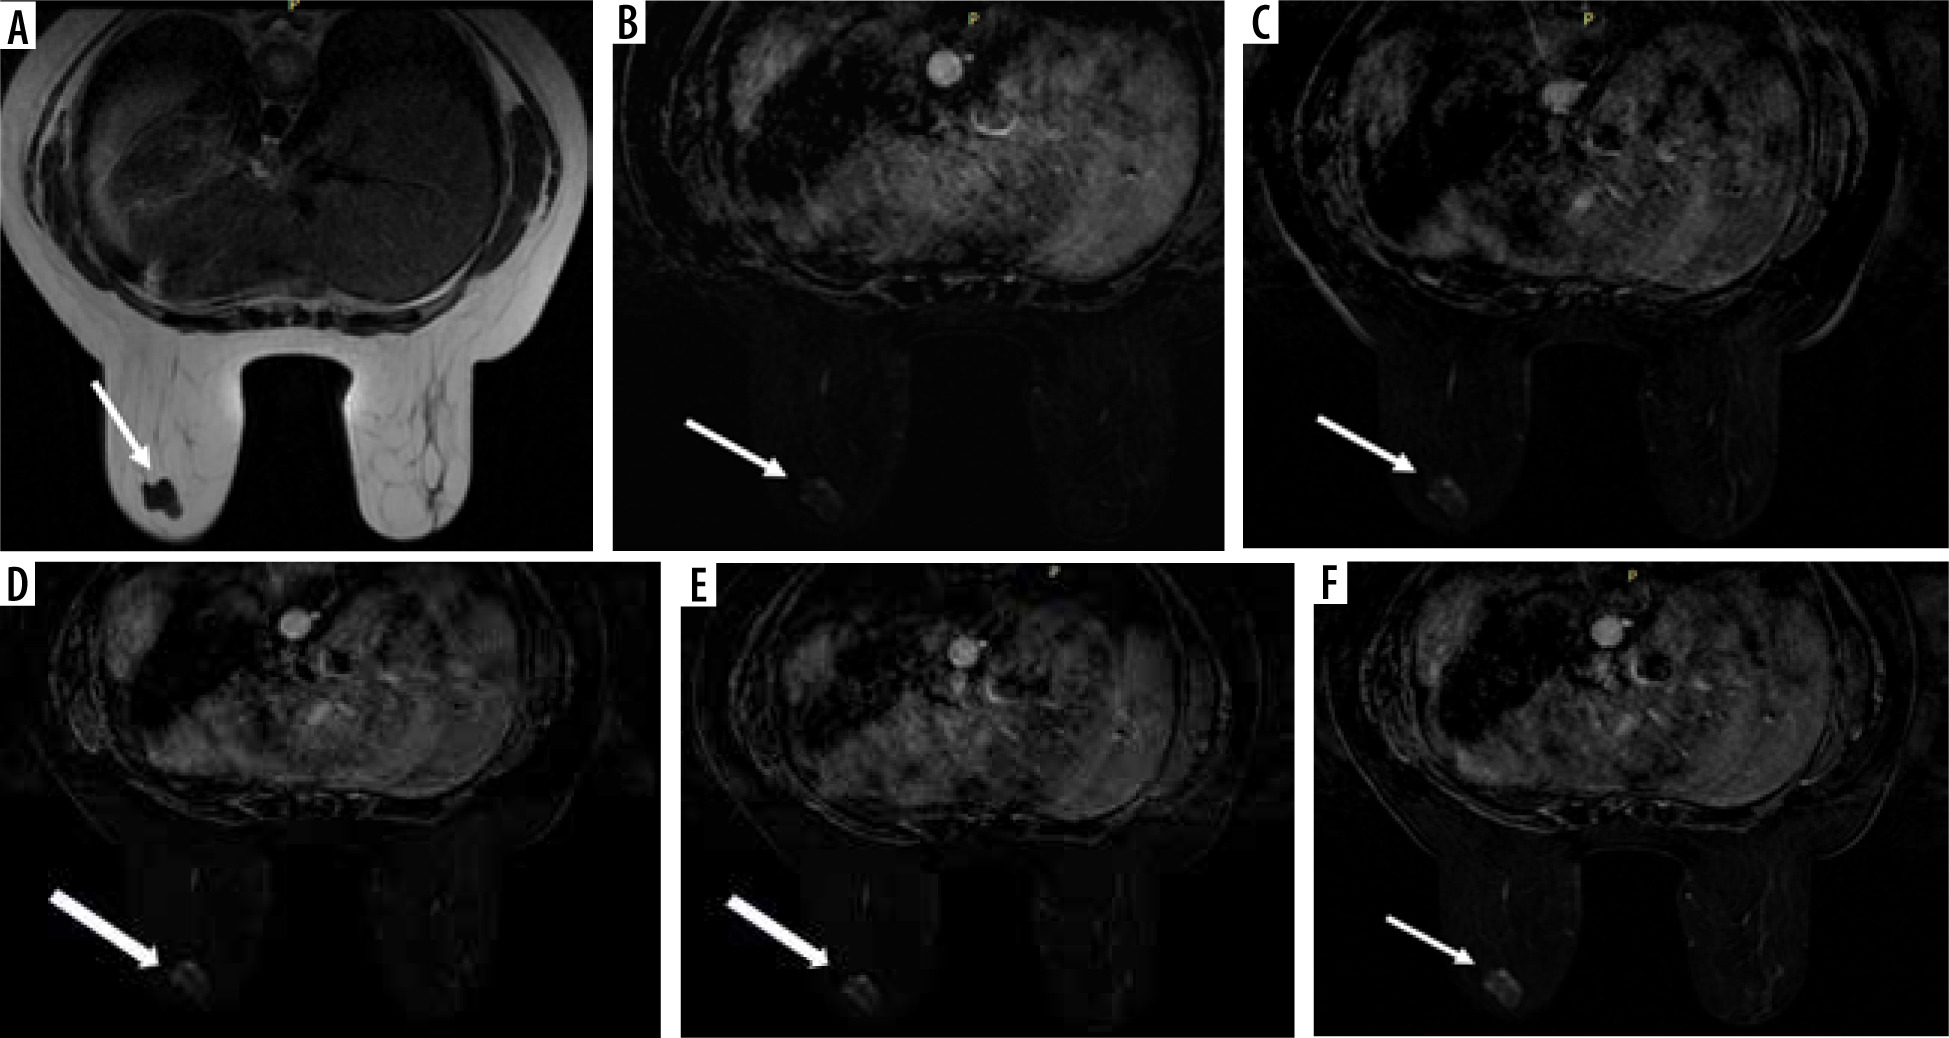

A 35-year-old female with left breast lump (full diagnostic protocol). A) Axial T2WI shows well defined lobulated outline hypointense soft tissue mass lesion in the lower outer quadrant of the right breast (white arrow). B) Point 1 (28 s) post-contrast T1WI with fat saturation subtracted image shows early enhancement of the soft tissue mass (white arrow). C) Point 2 (84 s) post-contrast T1WI with fat saturation subtracted image shows increased enhancement of the soft tissue mass. D) Point 3 (196 s), Point 4 (140 s), and Point 5 (252 s) post-contrast T1WI with fat saturation subtracted images show progressive filling and enhancement of the soft tissue mass (white arrow). Histopathology revealed a diagnosis of fibroadenoma

Discussion